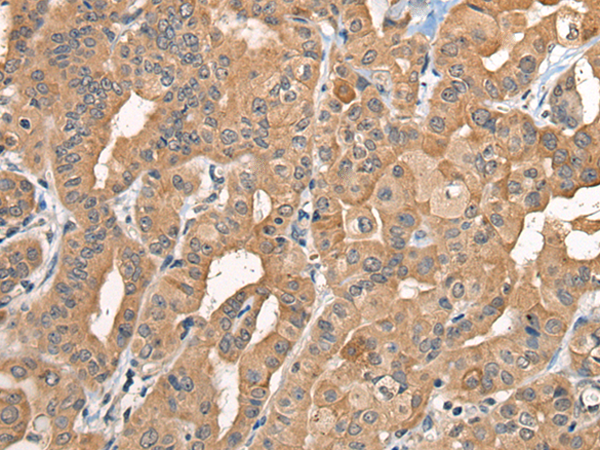

IHC positive control: |

Human thyroid cancer and human gastric cancer |